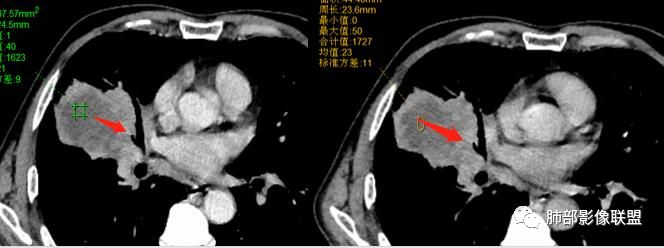

@吴婧南京市第一医院 这个从影像表现,坏死情况,以及叶裂推移情况与支气管推移情况来看,还是支持中叶间质来源,外朝内生长,同时向上,向下,向内都有推移作用。

具体的病理类型,把握真的不大,所以我也不勉强,如果非要猜一下的话,整个符合外朝内生长的肿瘤,所以我把肉瘤或肉瘤样癌排前面,低分化腺放后面,鳞癌可能性不大(生长位置不对,支气管堵塞情况不支持,纵隔内淋巴结肿大也不符合鳞)

下半段斜裂推移朝下

水平裂推移朝上

定在中叶应该没问题

上叶应该是侵犯,下叶应该是叶裂漏出来的。

1.具有肉瘤的特性:肿瘤体积一般较大,直径约大于5cm,边缘清楚、光整,由于肿瘤生长迅速,可见大片坏死,坏死边界清楚;常见支气管推移。

2.具有癌些特性:如分叶、短毛刺、空洞,但是钙化及胸膜凹陷征少见,病灶往往是直接侵犯胸膜,可以远处转移,肺门及纵隔淋巴结可明显肿大;

3.强化方式:增强后病灶以环状强化为主,病灶周边多以癌组织为主,血供丰富,病灶中心区则以肉瘤成分为主,血供较差,易出现粘液样变性、坏死、出血,坏死边界清楚,所以增强CT对PSC与普通型肺癌有一定的鉴别价值。

1.本病例结合病理结果及影像综合分析,应该符合肉瘤样癌,上皮成分是腺癌为主;肿块的边缘毛刺、分叶及周围癌型淋巴管炎征象有符合腺癌的影像表现之处。

2.肿块巨大局部边缘膨隆、光整,坏死较彻底;明显跨叶生长(途经发育不全叶间裂或肺门,注意患者没有胸水),支气管阻塞伴推移等,这些更符合肉瘤的特性。

3.坏死区边界较清楚(皮囊样),环形强化明显,病灶内血管穿行等,都不符合我们常见的鳞癌。